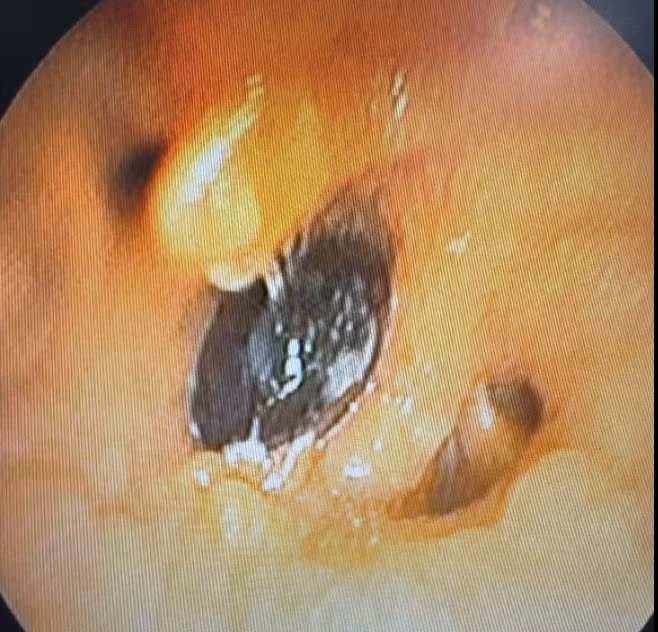

Kết quả chụp cắt lớp vi tính ghi nhận hình ảnh bất thường tại phế quản phải. Nội soi phế quản sau đó phát hiện một dị vật là hạt hồng xiêm kích thước hơn 2cm nằm ở phế quản thùy dưới phải, gây chít hẹp lòng phế quản, kèm tổ chức hạt và viêm phổi hậu tắc.

hat.jpg

Hạt hồng xiêm được lấy ra - Ảnh BVCC